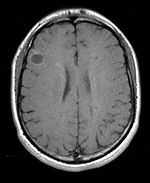

Unregistered baseline data: PD vs. T1Gd Unregistered followup data: PD exam 2 vs. exam 1

Registered baseline data Registered followup data